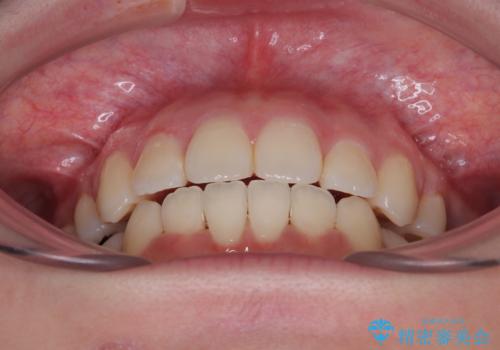

- 下の前歯のデコボコと、口元の突出感を改善したいと来院された患者様です。

上下左右の第一小臼歯を抜歯して、目立ちにくいワイヤー装置で矯正を行いました。

上下の保定用マウスピースの他に、デコボコの強かった下顎前歯にはワイヤーで保定をしています。